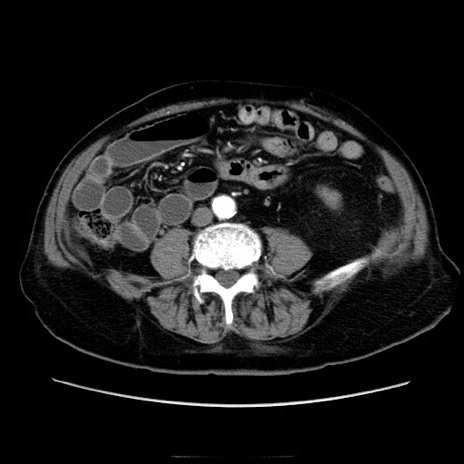

冠状断像

【症例】70歳代男性

【主訴】腹痛

【現病歴】肝硬変・肝細胞癌にてかかりつけの方。約9時間前に食後より腹痛出現。症状が徐々に増悪し、嘔吐出現したため来院。

【既往歴】肝硬変、肝細胞癌(RFA、TACE後)

【身体所見】意識清明、表情苦悶様、BT 36℃、BP 129/78mmHg、P 88bpm、SpO2 97%(RA)、右上腹部から心窩部にかけて圧痛あり、反跳痛なし、筋性防御あり。

【データ】WBC 5800、CRP 0.16